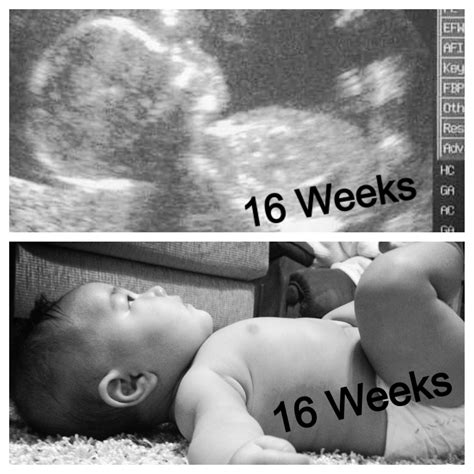

Ultrasound 16 Week

Pregnancy is an exciting journey filled with milestones, and one of the most anticipated is the Ultrasound 16 Week scan. This crucial checkpoint offers expectant parents a glimpse into their baby's development and provides valuable information for healthcare providers. Understanding what to expect during this ultrasound can help alleviate anxiety and enhance the overall experience.

By the time of the Ultrasound 16 Week scan, the baby has reached several significant developmental milestones:

• Size: The baby is about the size of an avocado, measuring approximately 4.5 to 5.4 inches (11.4 to 13.7 centimeters) in length and weighing around 3.5 ounces (100 grams).

• Senses: The baby's senses are developing rapidly. Eyelids remain fused shut, but the eyes can perceive changes in light. The baby can also hear sounds from the outside world.

• Movement: The baby becomes more active, with increased kicking, punching, and rolling movements.

• Organ Development: The baby's organs are forming, and the liver and pancreas are producing essential hormones.

• Lanugo: A fine hair called lanugo covers the baby's body, providing protection in the womb.